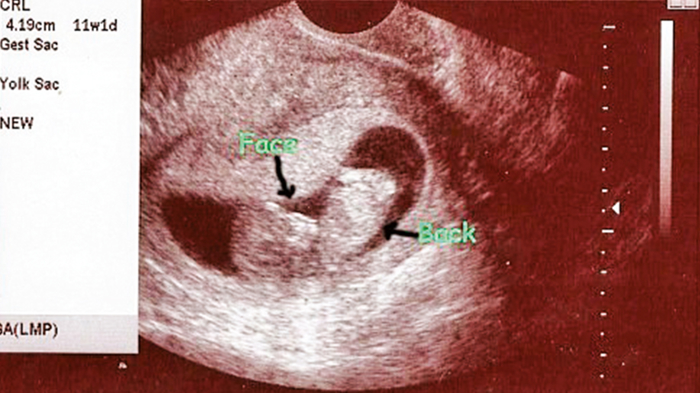

Peru'da 19 yaşındaki genç kadın, gebeliğin rahim yerine karaciğerin içinde gelişmesine rağmen sağlıklı bir bebek doğurdu. Karaciğerde büyüyen bebek, dünyada anne ve bebeğin birlikte hayatta kaldığı 4. vaka olarak kayıtlara geçti. İlginç vakanın detayları karşınızda...

Tıpta 'karaciğer dış gebeliği' olarak adlandırılan, döllenmiş yumurtanın rahim yerine karaciğer dokusuna yerleşmesiyle oluşan nadir bir durum, Peru'da hayata tutundu. Carlos Lanfranco La Hoz Hastanesi'nde sezaryen operasyonla doğum yapan 19 yaşındaki kadının, 3.6 kilo ağırlığında bebeği 40. haftada dünyaya geldi.

Bu, Peru'da ilk kez başarıyla sonuçlanan bir karaciğer dış gebelik vakası olurken, dünya genelinde de anne ve bebeğin birlikte hayatta kaldığı dördüncü vaka olarak tarihe geçti.